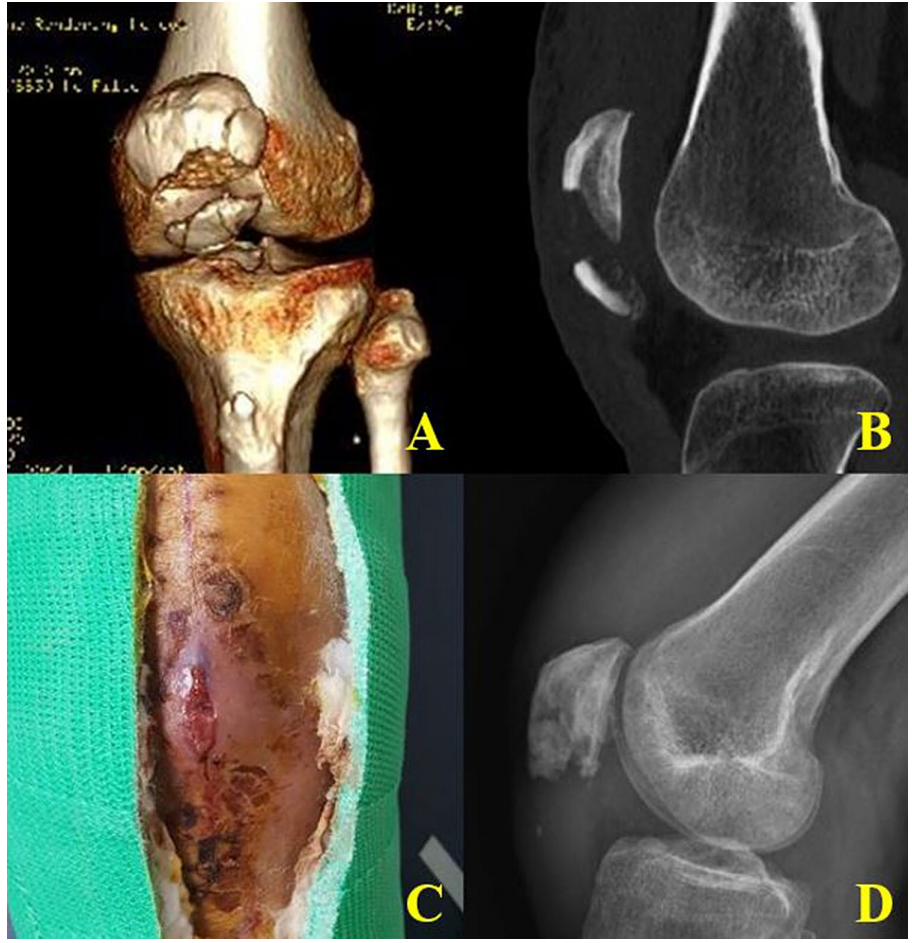

图5 一例骨膜套袖撕脱性髌骨骨折患者,术后4年随访X线片显示Insall–Salvati比值为0.38(髌骨低位)。然而,活动范围为0-130°,IKDC评分为71,Lysholm评分为85,KOOS评分为82。并且,她仅偶尔有膝前疼痛

我们使用Insall–Salvati比值评估髌骨的上-下位置。与正常膝关节相比,患膝的Insall–Salvati比值平均为0.73,该小于0.8的比值意味着髌骨低位(表2)。特别是,在1例髌骨下极骨膜套袖撕脱骨折患者中(图6),缝线锚钉固定后4年随访时,Insall–Salvati比值为0.38(髌骨低位)。活动范围为0-130度。IKDC评分为71,Lysholm评分为85,KOOS评分为82。她对最终临床结果非常满意,仅偶尔有膝前疼痛。组内相关系数(ICC)及95%置信区间(CI)为0.980(0.951-0.992)( p<0.05)。评估者间可靠性的ICC及95% CI为0.972(0.940-0.988)( p<0.05)。

图6 一例髌骨骨膜套袖撕脱骨折患者。X线片和3D CT显示髌骨下极粉碎性骨折(a, b)。MRI清晰显示髌骨骨膜套袖撕脱骨折(箭头)。缝线锚钉固定后4年随访时Insall–Salvati比值为0.38(髌骨低位)(D)